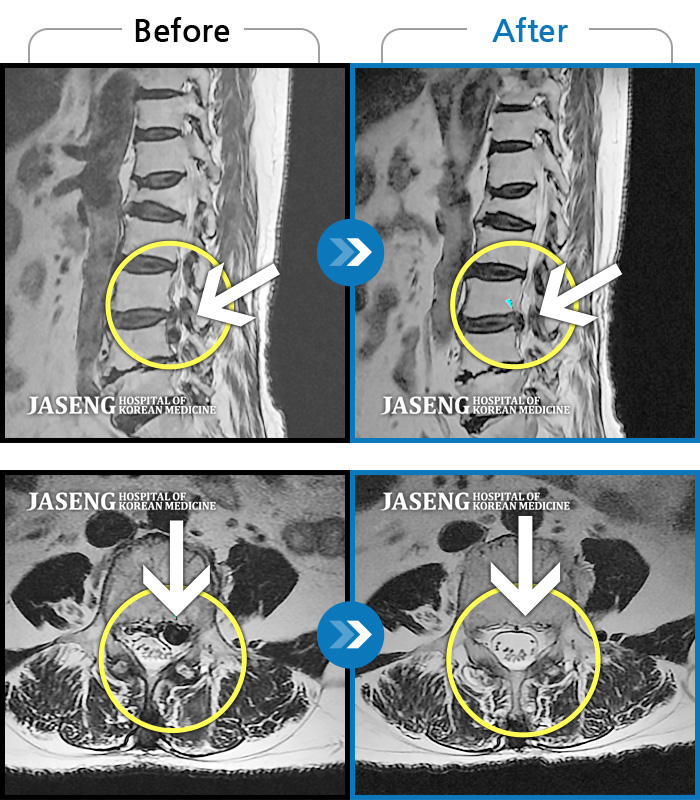

허리디스크

보라매 · 왕오호 원장

허리 통증, 똑바로 서려고 하거나 걸을 때 양쪽 허벅지와 고관절 시큰거림

촬영시기

2017.06.07 ~ 2018.04.17